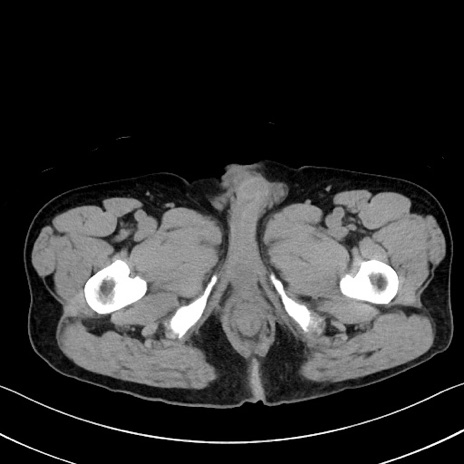

症例35(横断像)

【症例】70歳代 男性

【主訴】腹部膨満、嘔吐

【現病歴】昨日より腹部膨満感出現。本日増悪し、仙痛出現。嘔吐あり、受診。

【既往歴】糖尿病、胆摘後

【身体所見】BP 149/80mmHg、HR 74/min、BT 35.9℃、腹部:膨満、軟、圧痛なし。腸雑音減弱あり。上腹部正中切開瘢痕あり。

【データ】WBC 13500、CRP 1.72